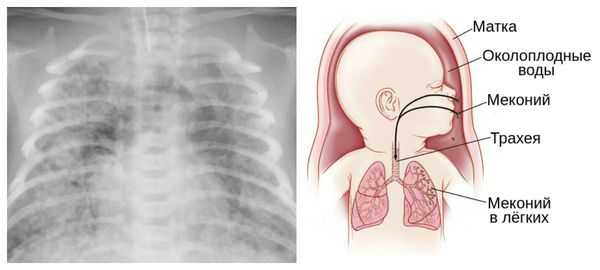

Из-за снижения кровотока в почках плода выделение мочи значительно уменьшается, развивается маловодие. Также изменяется характер околоплодных вод: они теряют прозрачность, становятся мутными, приобретают желтоватый или зеленоватый оттенок из-за примеси мекония — первых фекалий ребёнка.

За счёт изменения состава околоплодных вод нарушается выработка сурфактанта — вещества, которое не даёт альвеолам слипаться во время выдоха. Это вызывает патологию лёгочной ткани и нарушение дыхания после рождения. Также снижается защитная функция лёгких: в водах увеличивается число бактерий, что повышает риск инфицирования лёгочной ткани [1] [8] [11] .

Осложнения перенашивания беременности

Для плода большую опасность представляет асфиксия (острая гипоксия) и отслойка плаценты. Нехватка кислорода внутри утробы стимулирует плод выполнить несвоевременные дыхательных движения. Они приводят к заглатыванию вод и возможному воспалению лёгочной ткани — пневмониту. Если в водах есть примесь мекония (первородного кала), то велика вероятность мекониальной аспирации — проникновения содержимого кишечника новорождённого в его лёгкие.